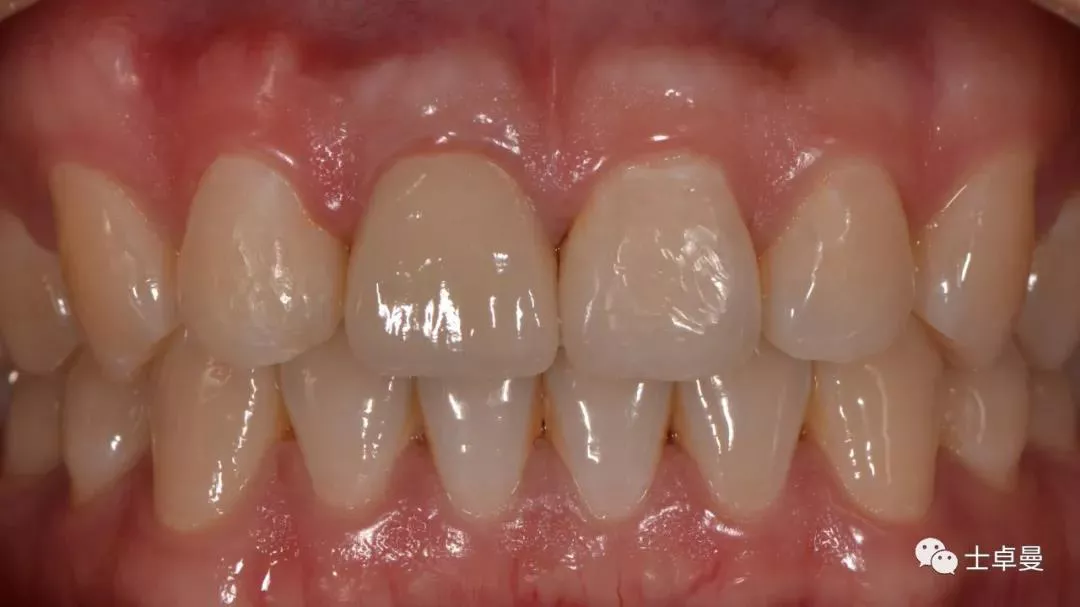

· 2个月后,见唇侧骨弓轮廓可,龈缘及龈乳头形态自然,去11临时修复体,植体ISQ值测定82,个性化取模,试戴Variobase氧化锆基台+LAVA氧化锆单冠,就位被动性良好,增加基台扭力至35Ncm,粘接固位上部冠,调合抛光。

完成永久修复,骨弓轮廓、龈缘及龈乳头形态自然,可见牙龈点彩,修复体外形及色泽可,患者满意。